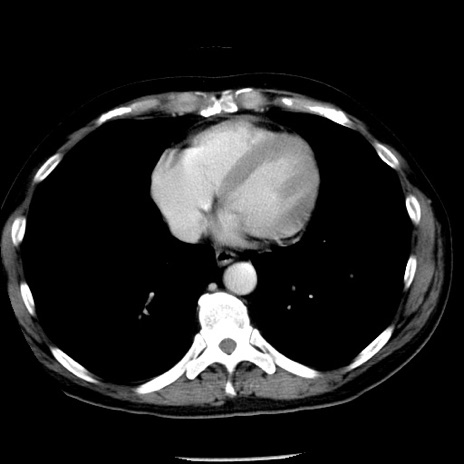

症例29(横断像)

【症例】40歳代男性

【現病歴】2日前から胃痛あり。徐々に周期的な激痛に変化した。本日になっても激痛があるため受診。

【身体所見】意識清明、BT 38-39℃台あり、腹部:膨満、やや硬、右下腹部に圧痛あり。

【データ】WBC 8500、CRP 23.26